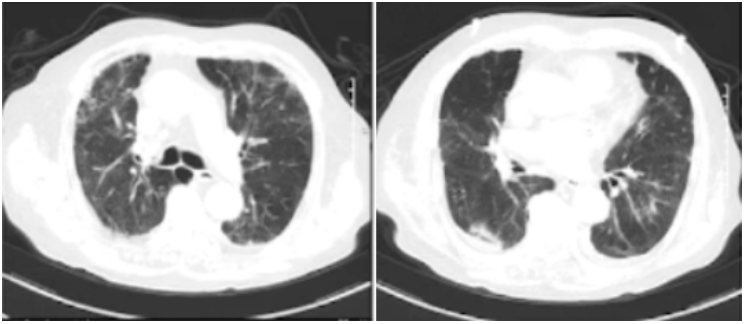

患者体温正常,但气促进行性加重,面罩吸氧10 L/min仍然呼吸窘迫,呼吸频率30~40次/min,查体可闻及肺部弥漫性细湿啰音。2023年1月9日床边胸片提示双肺间质性改变,右上肺明显(图2),IL-6、CRP、D-二聚体均进行性上升。复查新冠核酸阴性。

图2  床边X线胸片(2023-01-09)